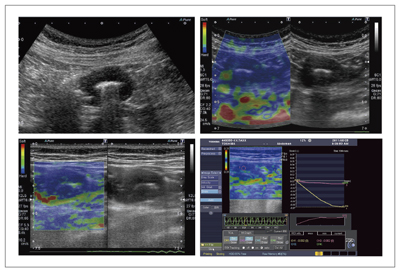

“Elastography”のリアルタイム表示による性状診断

Aplio500では,Real Time Application Platformによって処理能力が向上し,従来は不可能だったElastographyのリアルタイム表示が可能になった。加えて,コンベックスプローブによるElastographyが可能で,腹部領域におけるElastographyの適応範囲の拡大が期待される。

Elastographyは,プローブを軽く圧迫・解放することで,病変部位の硬さ(弾性)を画像化する。例えば,大腸がんの症例で,これに合併した閉塞性腸炎を来した場合,腸管浮腫の中に腫瘍が存在するといったケースが発生し,Bモード像では腫瘍の位置の特定は困難であるが,Elastographyを行うと腫瘍は硬い部位として認識され,容易に病変部の特定ができる。

図6は,Aplio500による小腸腫瘍のBモード画像である。Elastography(図7)を施行したところ,腫瘍は硬く,口側の柔らかな部位は正常小腸と病変部の境界であった。この部位に注目して詳細にBモード画像を観察していくと,内腔は保たれ,腸管の長軸方向へ腫瘍の進展像が見られた。腫瘍部は全域にわたり均一な低エコー像を呈していた。この一連の検査の流れの中で小腸リンパ腫の特徴的なエコー所見が得られ,診断に至った。